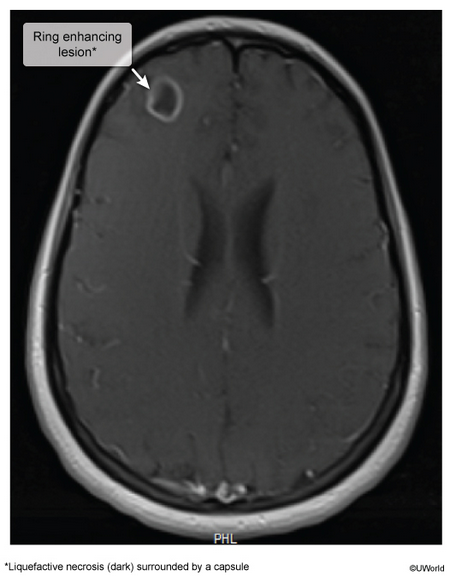

22yo with new generalized tonic-clonic seizure, 3-week hx progressive headaches, fever, nasal congestion, & rhinorrhea. HIV -.

brain abscess

likely staph a, viridians strep, or anaerobes

hiv+, sometimes missed prophy, 2 weeks of headaches and confusion. friends say he’s aggressive and suspicious, which is not normal for him.

toxoplasma, can reactivate if cd4 <100

could be tx/prevented with tmp-smx